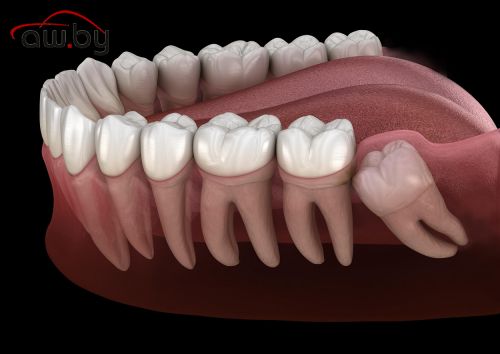

- Зубы мудрости, вызывающие осложнения. Неправильное положение третьих моляров может приводить к воспалению десны, смещению соседних зубов и боли.

Удаление может быть простым или сложным. Простое удаление проводится при хорошо видимом и доступном зубе, с применением местной анестезии. Сложное удаление — при глубоко расположенных или ретинированных зубах, травмах корня или костной ткани. В некоторых случаях требуется разрез десны или рассечение зуба на части для безопасного извлечения.